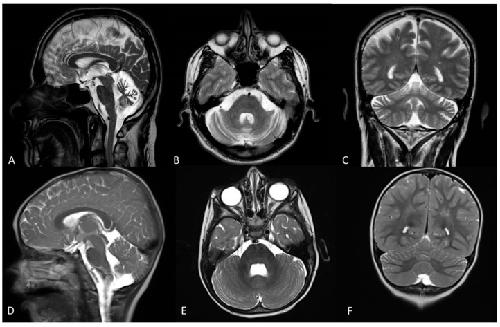

Figure 1. Brain MRI of patient 1 performed at 57 years old. T1-weighted midsagittal (A) axial (B) and coronal (C) sections showing atrophy of the cerebellar vermis and hemispheres. Brain MRI of patient 2 performed at age 2 years. T1-weighted midsagittal (D) axial (E) and coronal (F) sections showing mild atrophy of the superior cerebellar vermis and hemispheres.